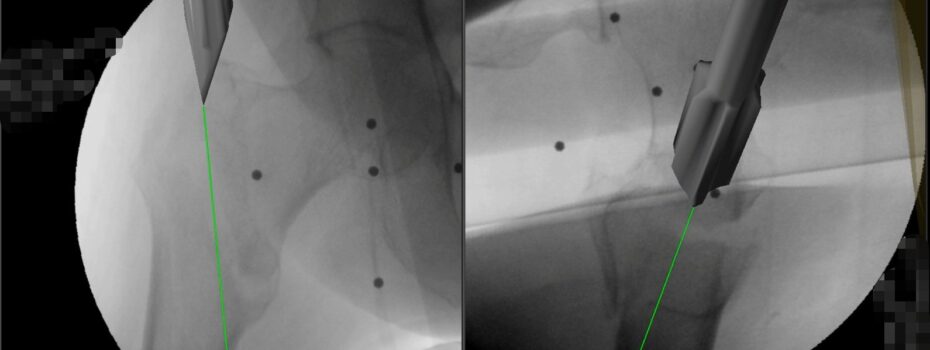

Trattare la frattura del femore utilizzando la realtà virtuale, preziosa “alleata” degli occhi e delle mani del chirurgo ortopedico. L’Ortopedia e Traumatologia dell’Ospedale “Di Venere” di Bari, con le prime 20 operazioni già eseguite con questo sistema tecnologico, ha varcato la nuova frontiera dell’innovazione applicata ad uno degli interventi preso a modello da Agenas per misurare la qualità […]